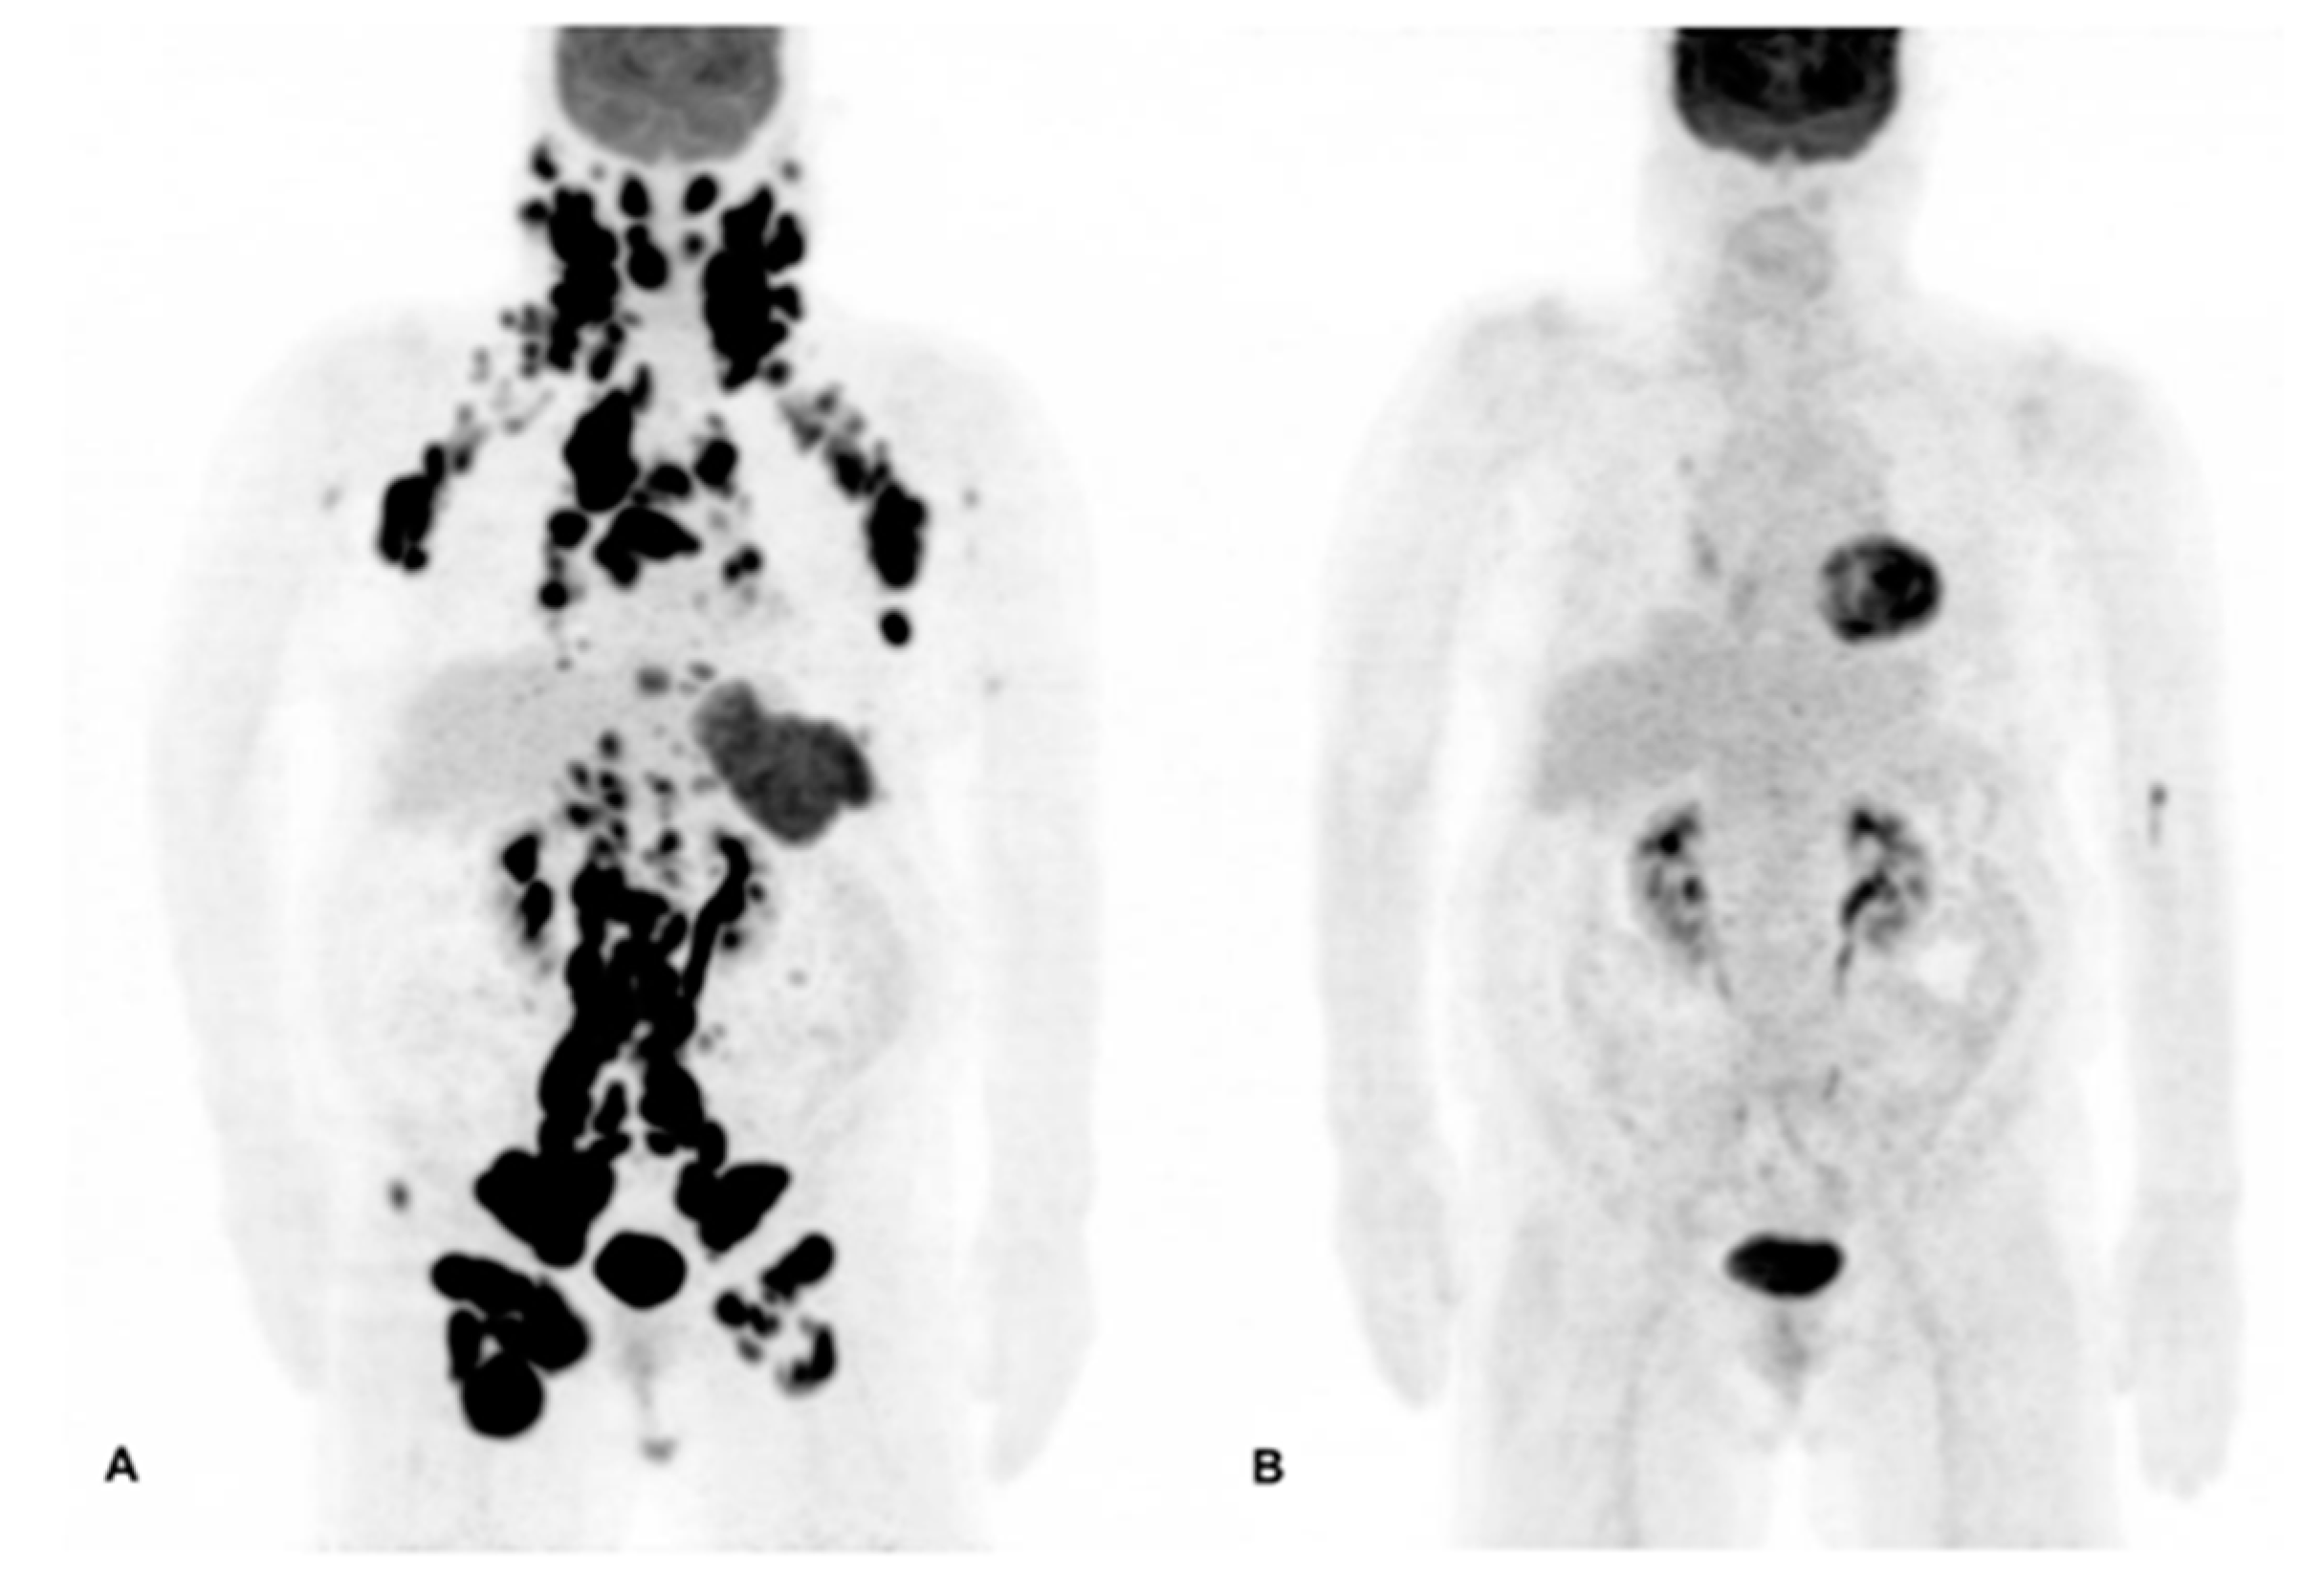

5.1. 18F-Fluorodeoxyglucose (FDG) PET/CT

- Bodet-Milin, C.; Eugène, T.; Gastinne, T.; Bailly, C.; Le Gouill, S.; Dupas, B.; Kraeber-Bodéré, F. The role of FDG-PET scanning in assessing lymphoma in 2012. Diagn. Int. Imaging 2013, 94, 158–168. [Google Scholar] [CrossRef] [PubMed]

- Cheson, B.D. Staging and response assessment in lymphomas: The new lugano classification. Chin. Clin. Oncol. 2015, 4, 5. [Google Scholar] [PubMed]

- Zijlstra, J.M.; Lindauer-van der Werf, G.; Hoekstra, O.S.; Hooft, L.; Huijgens, P. 18F-fluoro-deoxyglucose positron emission tomography for post-treatment evaluation of malignant lymphoma: A systematic review. Haematologica 2006, 91, 522–529. [Google Scholar] [PubMed]

- Meignan, M.; Gallamini, A.; Itti, E.; Barrington, S.; Haioun, C.; Polliack, A. Report on the third international workshop on interim positron emission tomography in lymphoma held in menton, france, 26–27 September 2011 and menton 2011 consensus. Leuk. Lymphoma 2012, 53, 1876–1881. [Google Scholar] [CrossRef] [PubMed]

- Swinnen, L.J.; Li, H.; Quon, A.; Gascoyne, R.; Hong, F.; Ranheim, E.A.; Habermann, T.M.; Kahl, B.S.; Horning, S.J.; Advani, R.H. Response-adapted therapy for aggressive non-hodgkin’s lymphomas based on early [18F] FDG-PET scanning: Ecog-acrin cancer research group study (E3404). Br. J. Haematol. 2015, 170, 56–65. [Google Scholar] [CrossRef] [PubMed]